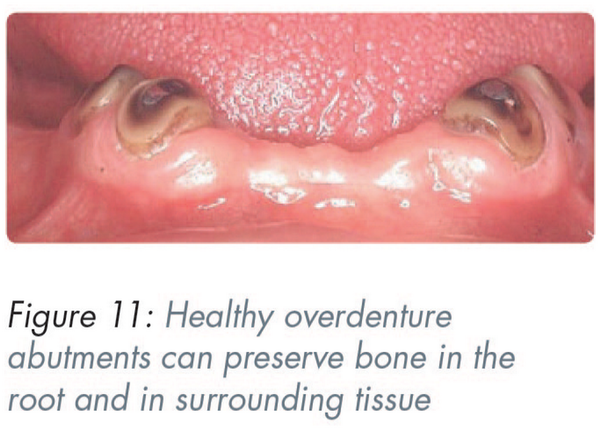

If kept healthy, it preserves the bone – not only that associated with the root but also of the surrounding tissues (Figure 11).

By supporting the saddle it prevents resorption due to occlusal forces. The lack of this support in the presence of plaque, often leads to so called “gum stripping” of the abutments.

The presence of the root surface positively identifies the position of the replacement denture tooth. This is extremely valuable where there is a doubt regarding the size/width of the replacement.